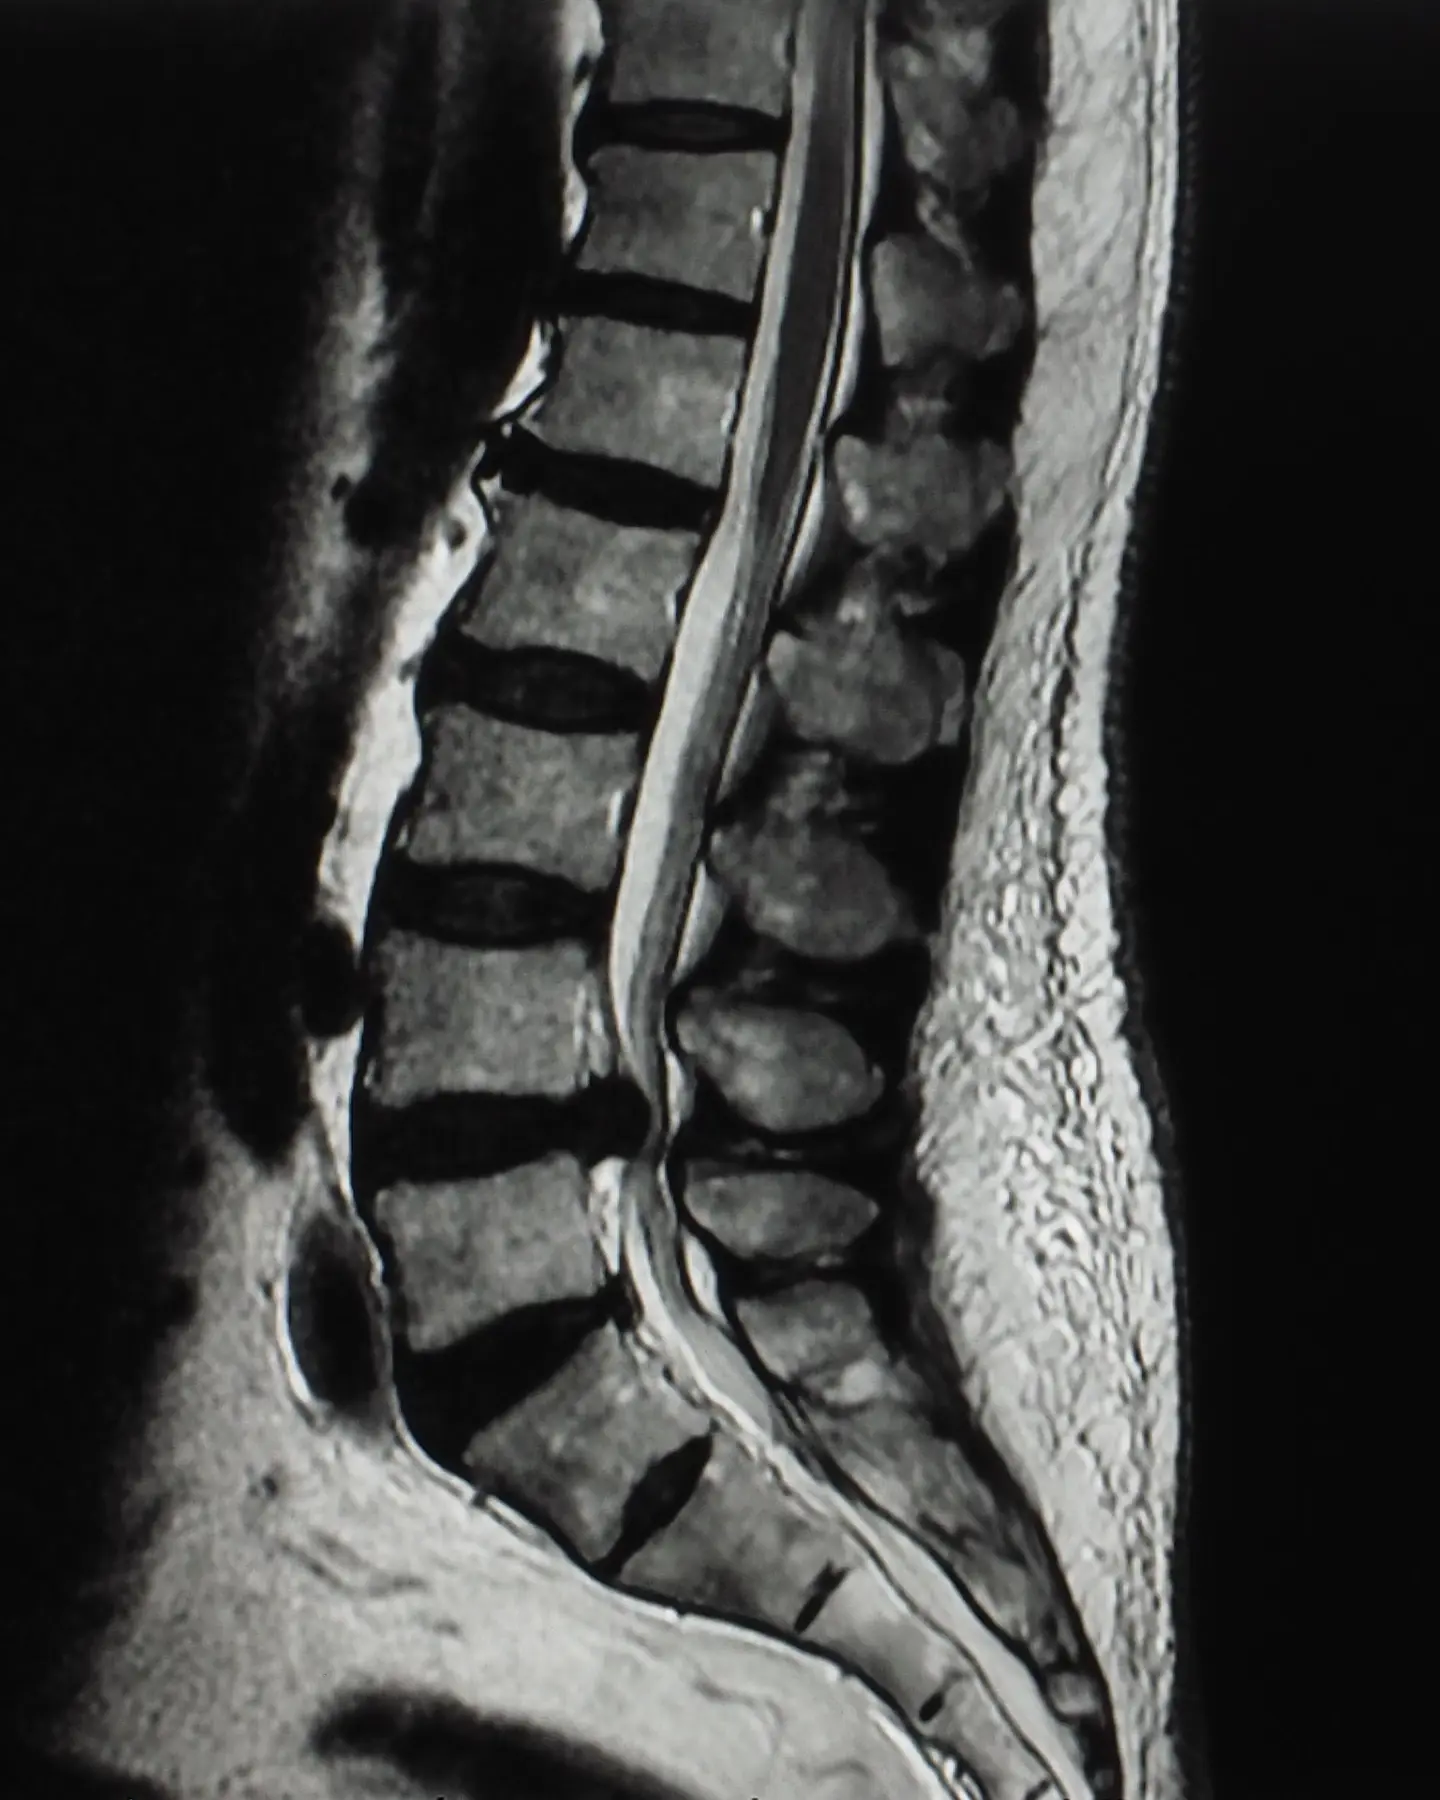

Diagnostic spine MRI scan

A spinal MRI scan can comprehensively assess the spine, including the lumbar, thoracic, and cervical regions, to identify any abnormalities or conditions affecting these areas.

MRI stands for Magnetic Resonance Imaging, which is a way of taking pictures inside the body using magnetic fields and radio waves. It’s a safe, painless and non-invasive procedure capturing high-quality images. Unlike X-rays, MRI doesn’t use potentially harmful radiation.

A spine MRI scan can focus on one of three defined areas of the spine, depending on your symptoms and where you’re experiencing pain.